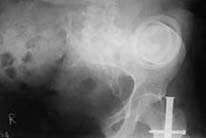

This young individual(a seond year medical student at that time) was brought to us four years ago with subtotal amputation of right hemipelvis and fracture left femur. He was treated with emergency right hemipelvectomy, emergency permanent sigmoid colostomy,ileal conduit for urinary diversion and external fixation for left femur. After he was stable and off ventillator interlocking left femur was done.

He was initially ambulated on a pair of crutches and later on a prosthesis specially made at Armed Force's Artificial Limb Centre, Pune. This prosthesis weighed 11.5Kg. Later when this developed problems another prosthesis weighing 9 Kg was made by a centre in Kerala (Lords). At present he has one prosthesis made by Endolite which weighs 4 Kg. However this is not quite satisfactory.